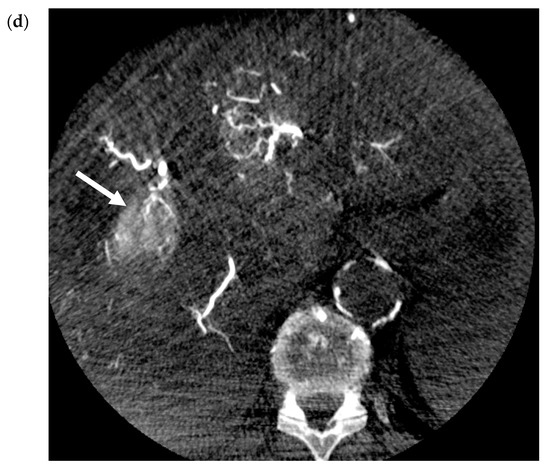

- Yoo, H.; Kim, J.-H.; Ko, G.-Y.; Kim, K.W.; Gwon, N.I.; Lee, S.-G.; Hwang, S. Sequential Transcatheter Arterial Chemoembolization and Portal Vein Embolization versus Portal Vein Embolization Only before Major Hepatectomy for Patients with Hepatocellular Carcinoma. Ann. Surg. Oncol. 2010, 18, 1251–1257. [Google Scholar] [CrossRef]

- Ogata, S.; Belghiti, J.; Farges, O.; Varma, D.; Sibert, A.; Vilgrain, V. Sequential arterial and portal vein embolizations before right hepatectomy in patients with cirrhosis and hepatocellular carcinoma. Br. J. Surg. 2006, 93, 1091–1098. [Google Scholar] [CrossRef]